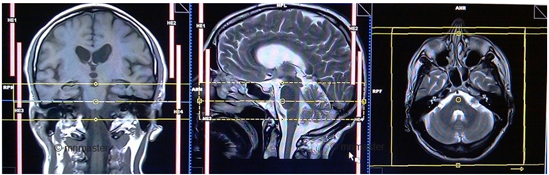

T2-space-3D axial